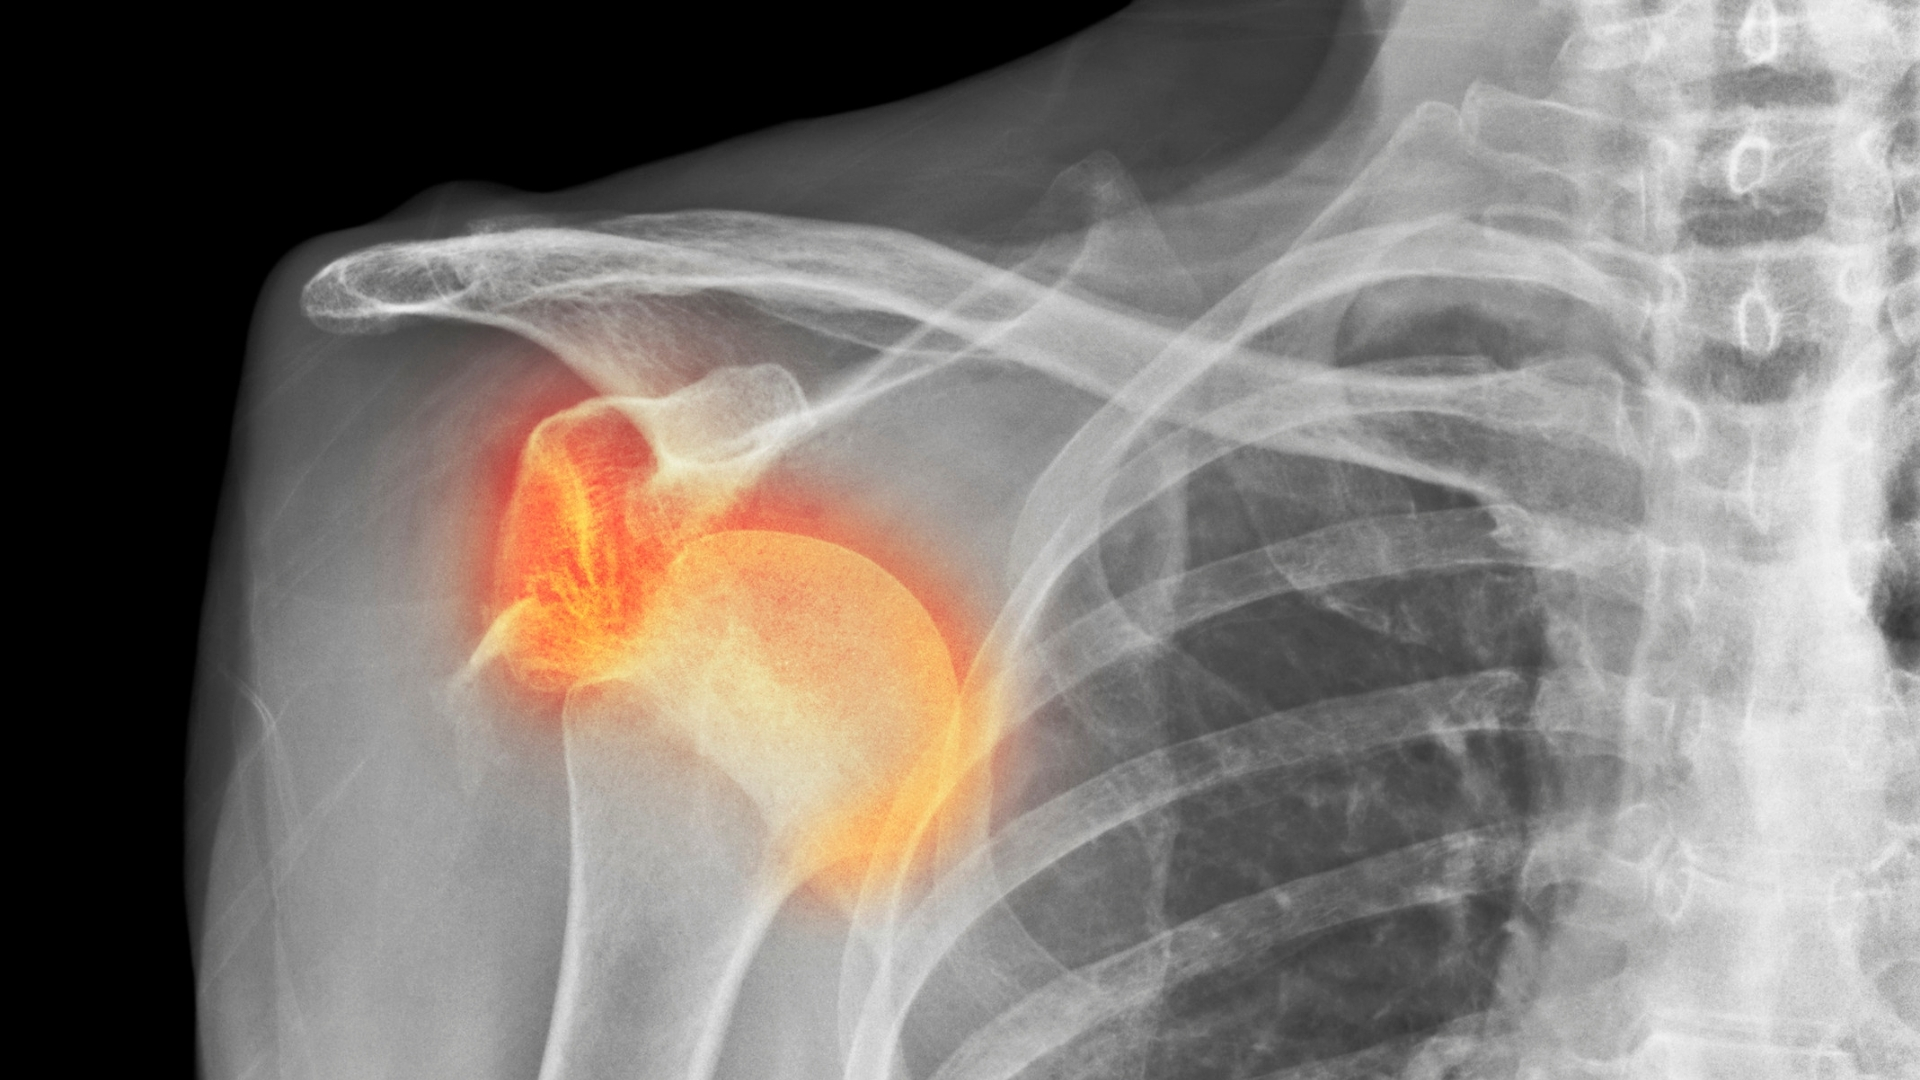

Trật khớp vai là tình trạng đầu xương cánh tay (xương cánh tay trên) bị lệch khỏi ổ chảo của xương bả vai, làm mất sự liên kết bình thường giữa hai cấu trúc chính của khớp vai. Đây là một trong những loại trật khớp phổ biến nhất trong cơ thể do khớp vai có biên độ vận động rộng nhưng lại ít được bao bọc chắc chắn. Khi trật, các dây chằng, bao khớp và mô mềm quanh khớp có thể bị tổn thương, gây đau dữ dội, mất khả năng cử động và có nguy cơ ảnh hưởng đến thần kinh hoặc mạch máu vùng vai.

Dấu hiệu trật khớp vai bao gồm cảm giác đau nhói đột ngột, khớp vai biến dạng và mất khả năng cử động bình thường. Một số trường hợp còn kèm theo sưng nề, bầm tím hoặc tê bì cánh tay do tổn thương dây thần kinh và mạch máu xung quanh khớp.

- Biến dạng vùng vai: Vai bị trật thường có hình dạng bất thường, bên vai tổn thương có thể trông thấp hơn, xệ xuống hoặc nhô ra phía trước so với bên còn lại. Đây là dấu hiệu rõ ràng nhất giúp nghi ngờ trật khớp vai.

- Sưng nề và bầm tím: Sau vài giờ, vùng vai có thể bị sưng lên kèm theo vết bầm tím lan rộng. Tình trạng này là do tụ máu và phản ứng viêm sau chấn thương.

- Tê hoặc ngứa ran ở cánh tay: Trật khớp vai có thể ảnh hưởng đến dây thần kinh, gây ra cảm giác tê bì, ngứa ran hoặc yếu cơ ở cánh tay và bàn tay. Đây là dấu hiệu cần theo dõi kỹ để tránh biến chứng thần kinh.